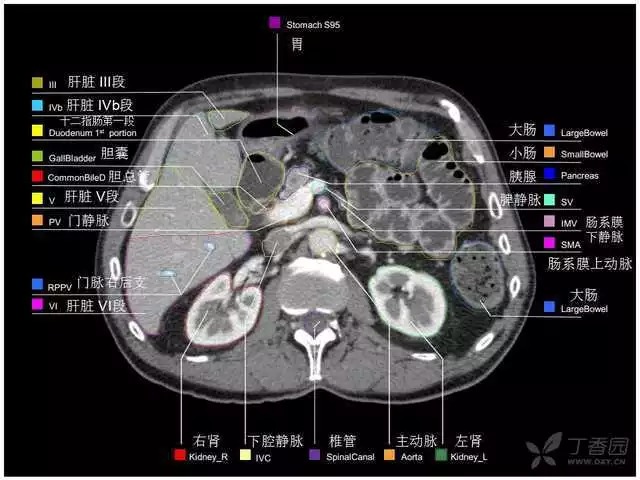

腹部肝脏高清CT断层的图谱

全腹部高清CT图谱,淋巴结彩色图谱,血管解剖图谱大汇总!